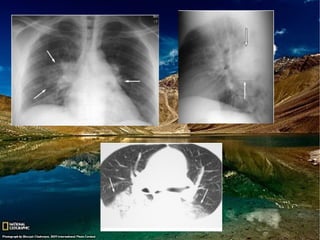

Achados de imagem

Radiografia de tórax:

Consolidação esparsa ou confluente uni ou

Afeta regiões pendentes dos pulmões;

Atelectasia(s);

Mendelson: consolidação bilateral difusa ou

Tomografia de tórax:

Opacidades em vidro fosco e consolidações

Nódulos centrolobulares ou nódulos acinares

Predomínio nas regiões pendentes dos

Pode ser visto fluido no interior dos brônquios.